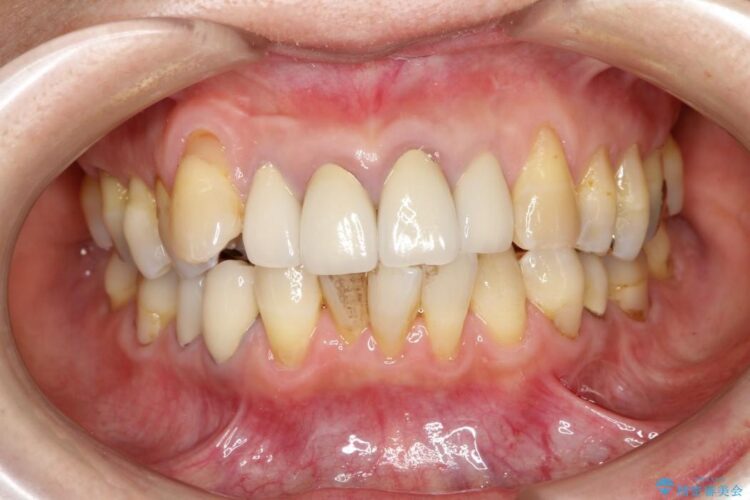

【30代男性】衝撃的なビフォーアフター!クリーニングで見違えるほどの白い歯に

【30代男性】衝撃的なビフォーアフター!クリーニングで見違えるほどの白い歯に ビフォー 【30代男性】衝撃的なビフォーアフター!クリーニングで見違えるほどの白い歯に アフター

歯の着色を綺麗にしたいとご来院されました。